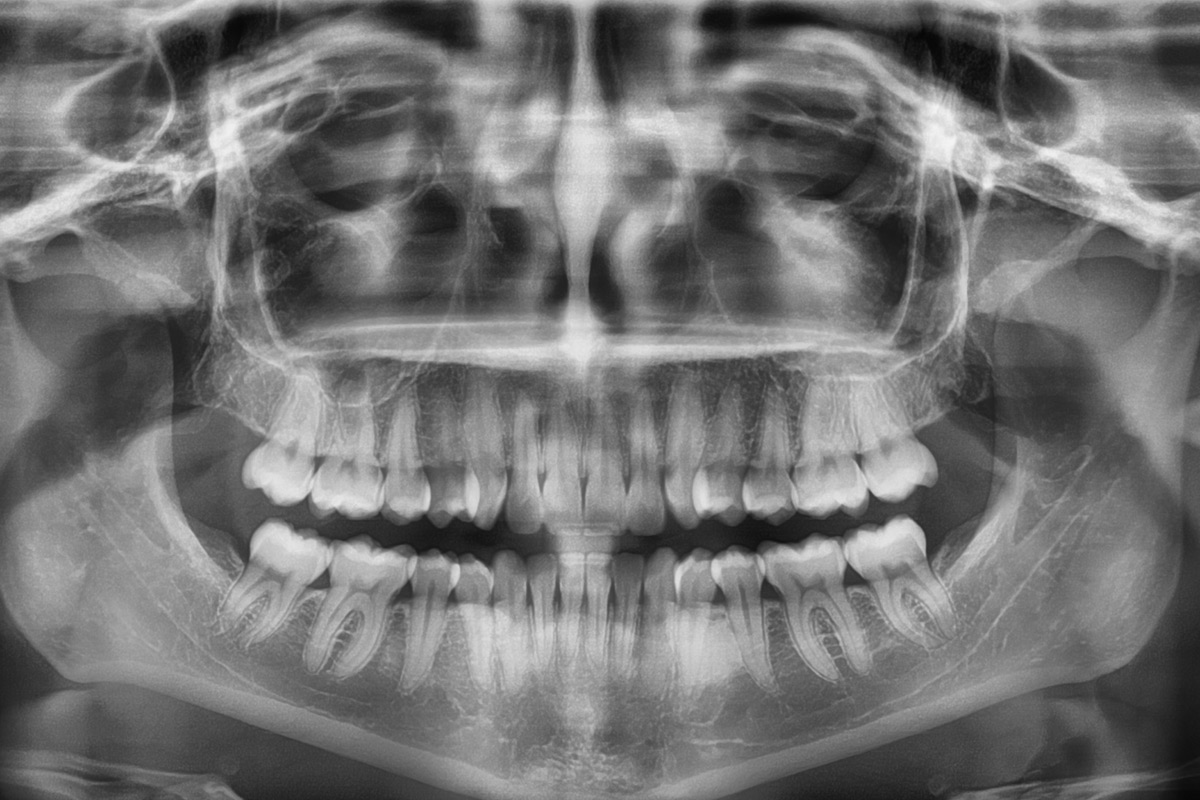

Radiografía Extraoral Digital

Esta tecnología digitalizada permite obtener imágenes de alta resolución en cuestión de segundos, con una exposición significativamente menor a la radiación en comparación con los métodos tradicionales de radiografía. Las imágenes obtenidas se almacenan electrónicamente, lo que facilita su análisis, almacenamiento y comparación con estudios anteriores para un seguimiento detallado del paciente.

Este tipo de radiografía es esencial en una amplia variedad de procedimientos odontológicos y maxilofaciales. Es particularmente útil en la evaluación de problemas que afectan a las estructuras dento-maxilo-faciales. Entre sus aplicaciones más comunes se encuentran la evaluación de la erupción de los dientes, la planificación de tratamientos de ortodoncia, la detección de fracturas o lesiones óseas, y el diagnóstico de enfermedades de la articulación temporomandibular (ATM). Además, es una herramienta valiosa para la planificación de cirugías maxilofaciales y en la evaluación previa a la colocación de implantes dentales.

- Ortopantomografía